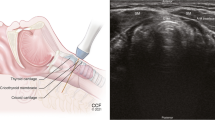

Airway Management

Endotracheal (ETT) Placement and Confirmation

Many proposed models of perioperative POCUS include the role of ultrasound for confirmation of ETT placement [2, 8••], either in real time imaging over the neck during intubation, or secondarily by detection of ventilation with signs of lung sliding or diaphragmatic movement. These studies have primarily been done for intubations in the emergency room rather than in the operating room, as the use of ultrasound for ETT confirmation would be most beneficial where capnography is not immediately available or noise prevents auscultation such as emergency room or pre-hospital settings.

Direct ultrasound confirmation of tracheal intubation is inferred from a single, hyperechoic air-mucosal interface (the trachea), whereas esophageal intubation creates two (both trachea and esophagus), or the “double tract sign.” This approach has shown comparable sensitivity and specificity to waveform capnography and clinical exam [53,54,55,56]. One meta-analysis that included 11 trials (n = 969 intubations) and reported both sensitivity and specificity of 98% [57]. Chou et al. also included cadaveric studies (n = 1656 intubations) with reported sensitivity and specificity of 93% and 97%, respectively [55]. Furthermore, because the patient’s lungs must be ventilated several times to confirm with capnography, transtracheal ultrasound allows for fast confirmation [53, 58, 59] and is as fast as auscultation alone, and faster than standard auscultation and capnography [60, 61].

Confirmation of ETT can also be done indirectly through identifying signs of lung ventilation including lung-sliding [62,63,64] and diaphragmatic motion through a subcostal view [65]. For secondary confirmation, bilateral assessment is important to avoid missing a mainstem intubation, and the patient cannot be spontaneously breathing. Table 6 summarizes basic principles of trancheal ultrasound.

Additional Airway Uses

As anesthesiologists become more trained in whole-body ultrasound, POCUS of the airway may continue to develop. It has been suggested ultrasound can provide a non-invasive version of the Cormack-Lehane classification as it has been shown to have a significant correlation between ultrasound evaluation and the epiglottis and vocal cords distance and may supplement current noninvasive modalities of pre-anesthetic airway assessment, such as the Mallampati Classification [69]. However, evidence for the ability to predict a difficult airway is inconsistent [70, 71]. Ultrasound may be useful to evaluate pathology affecting airway management such as laryngeal stenosis or cysts [17]. Using ultrasound to measure the width of the base of tongue has also been shown to predict severity of obstructive sleep apnea (OSA) [72]. Ultrasound can also be of use intraoperatively to perform airway nerve blocks, locate the cricothyroid membrane for emergency tracheostomy [73] and predict appropriate diameter for ETT through measurement of subglottic diameter [74]. Postoperatively, it can also be used to assess for subglottic edema [18], for instance in a patient with increasing postoperative distress. The use of POCUS for these and other topics in airway management is described more thoroughly by Kristensen [17] and Votruba and colleagues [18].